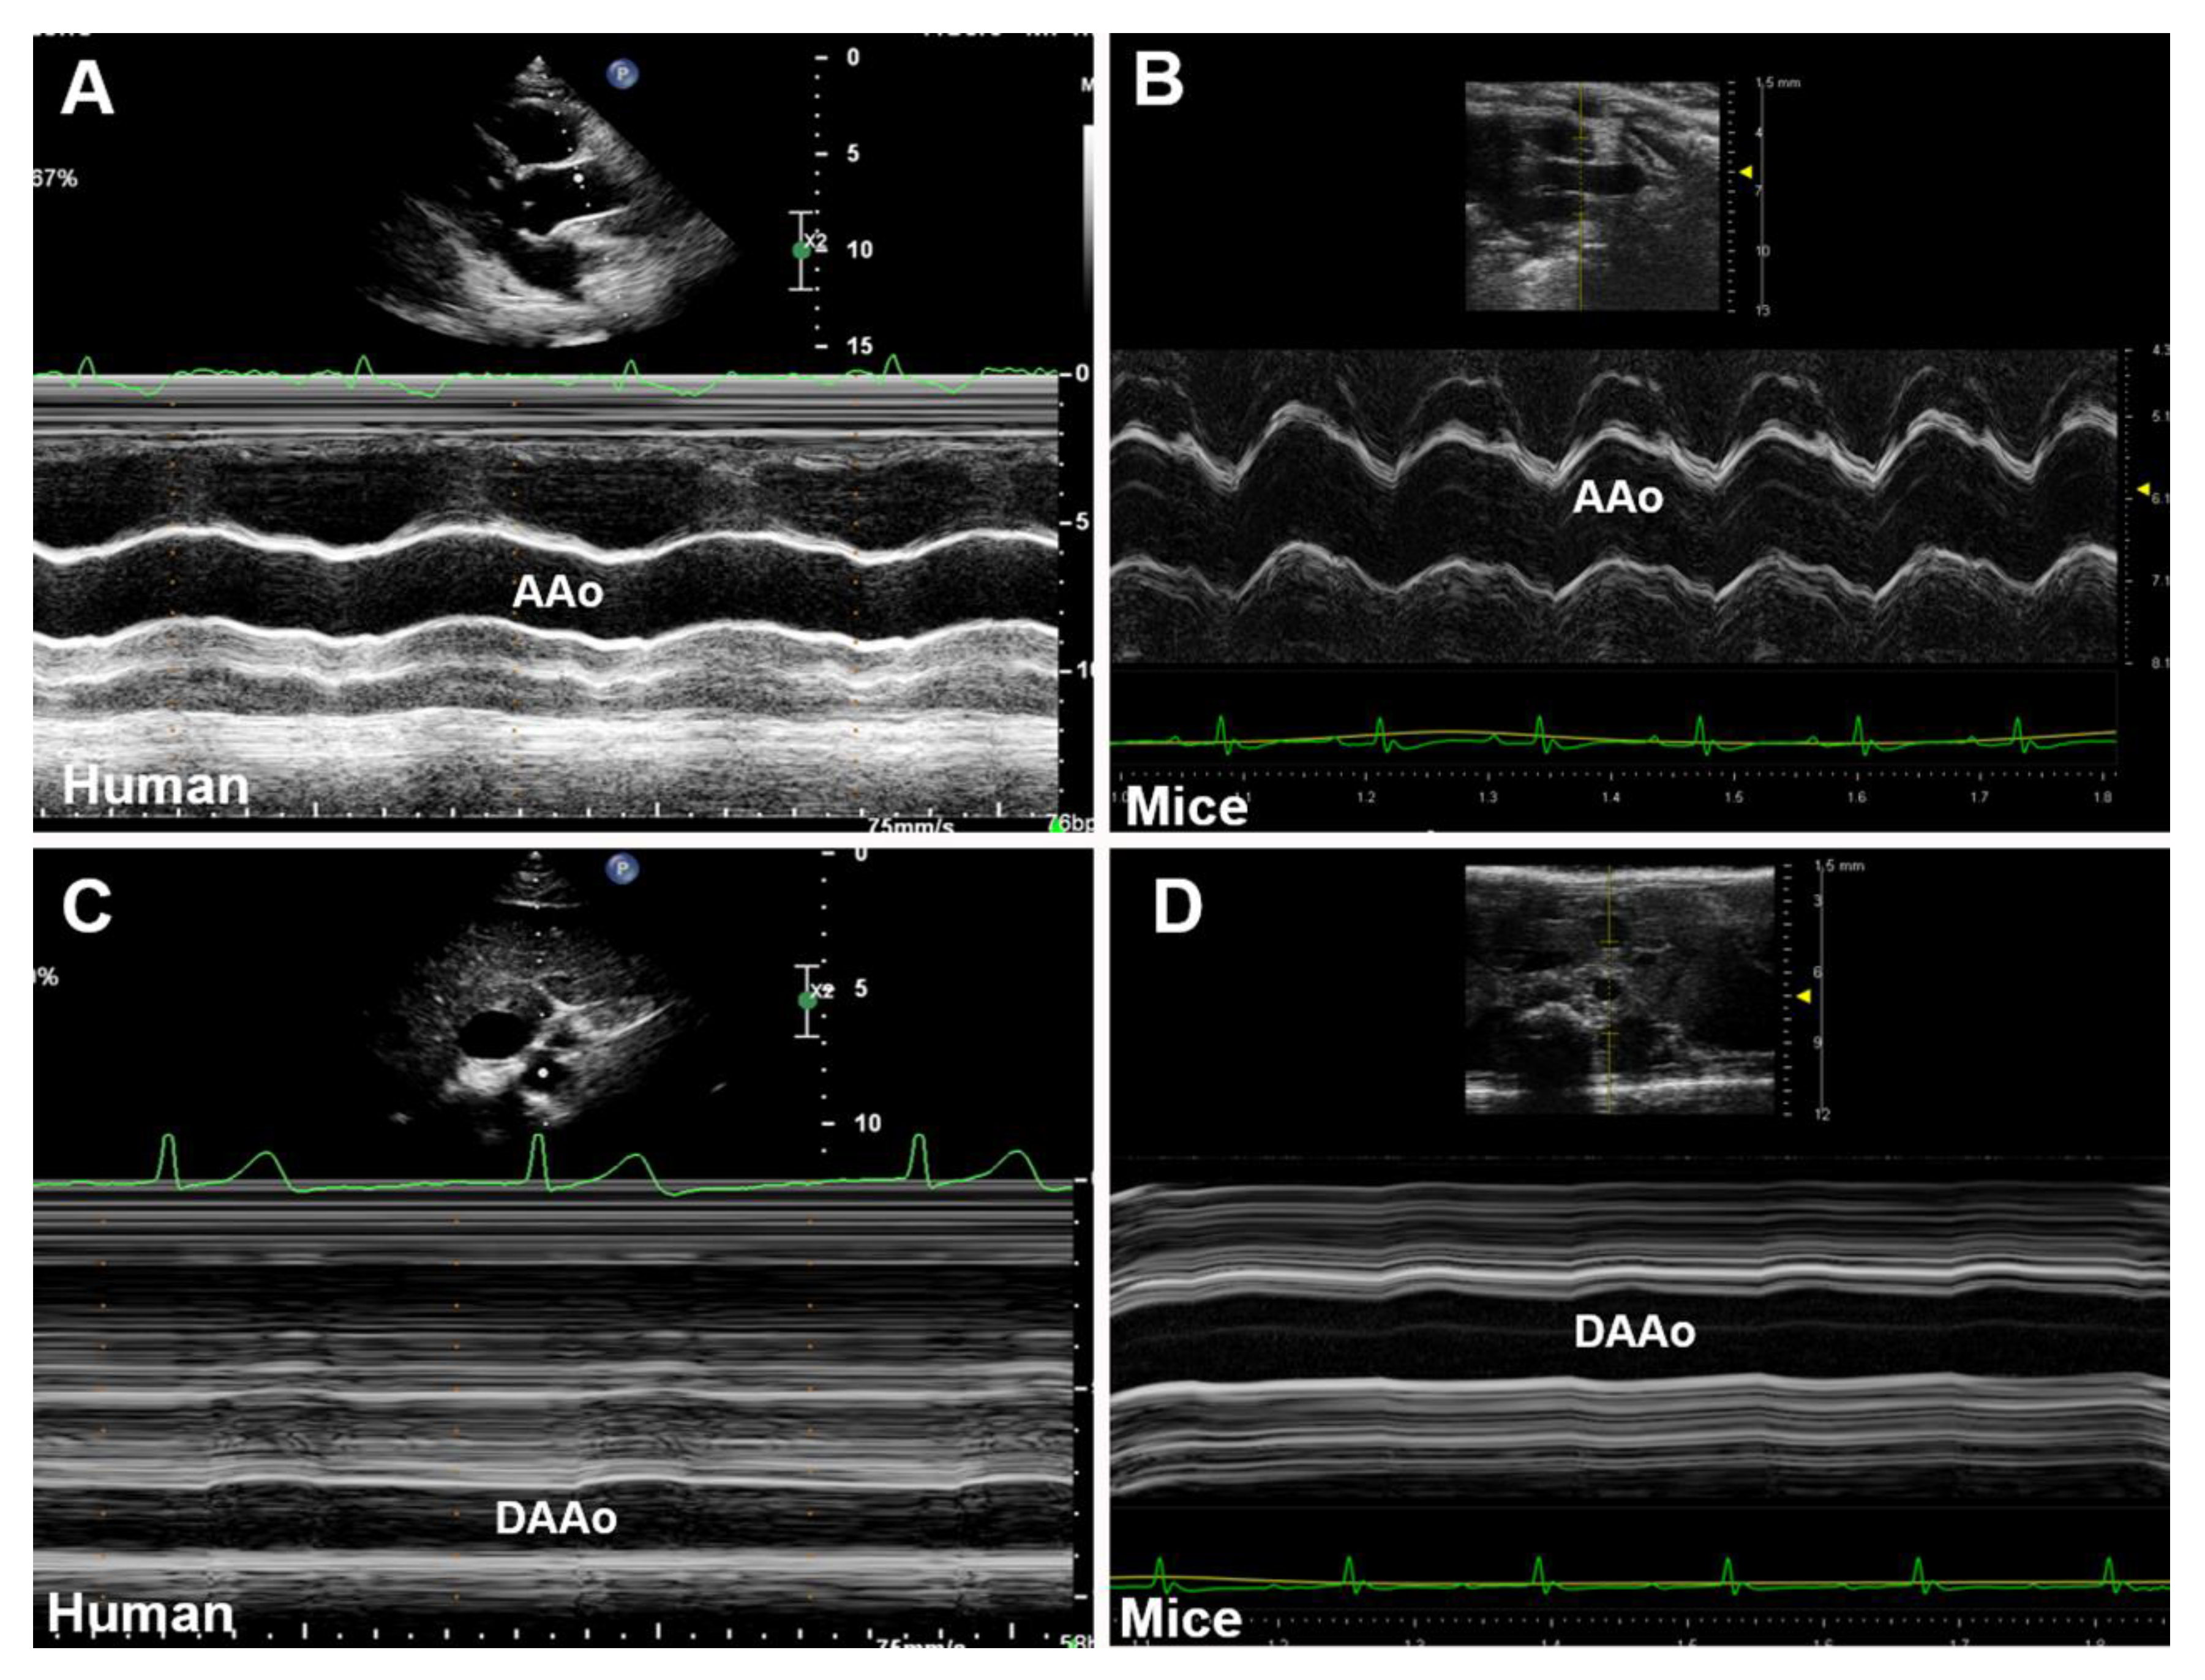

M-mode ultrasonography detects the structures along a single axis, by which the tissue interfaces are represented in dots on the display screen. With a high temporal resolution, M-mode images can measure the inner diameter and wall thickness of the aorta from several cardiac cycles. Thus, systolic and diastolic diameters could be obtained simultaneously [29]. As illustrated in Figure 2, an M-mode line can be placed perpendicular to the aortic walls, such as a long-axis view of the AAo (Figure 2A,B) and a short-axis view of the DAAo (Figure 2C,D). The image acquisition of the aorta by M-mode ultrasonography and its application in assessing aortic dimensions are similar between humans (Figure 2A,C) and rodents (Figure 2B,D).

Figure 2. Representative M-mode displays of the aorta for the anterior–posterior diameter measurement. (A,B): The long-axis view of the ascending aorta (AAo) obtained in systole and diastole in human (A) and mouse (B). (C,D): The short-axis view of the descending abdominal aorta (DAAo) in systole and diastole in humans (C) and a mouse model (D).